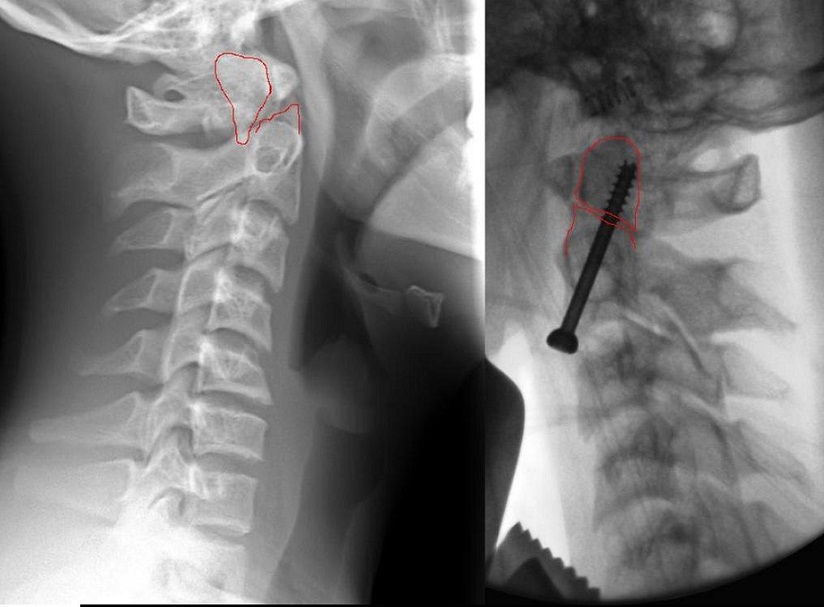

בתמונה: צילום השבר לפני הקיבוע (משמאל), ולאחריו (מימין).

הנער, שהגיע לפני כשבוע לחדר המיון עם חבלה בעמוד השדרה הצווארי, סבל משבר בלתי יציב בחוליה הצווארית השנייה, חבלה המוכרת יותר בשם "שבר במפרקת". חבלה כזו יכולה לגרום למוות כמעט וודאי, במקרה והשבר פוגע בחוט השדרה . למזלו של הנער, הפגיעה נגרמה בחוליה מסוימת, שאפשרה לרופאים להציל את חייו, אבל גם לספק לו איכות חיים גבוהה בהמשך, זאת הודות לניתוח חדשני שכמוהו בוצעו בודדים בארץ, ונעשה לראשונה בצפון, ובמהלכו בוצע קיבוע לשבר, באמצעות בורג בודד בלבד.

במקרה שכזה, מדובר בניתוח כירורגי מורכב עם סיכונים גבוהים למטופל. על-ידי בחירה באפשרות הבאה, הצליחו הרופאים לקבע את השבר באמצעות בורג בודד בלבד מאזור בסיס הצוואר, מקדימה מעל עצם הבריח, כשבדרך זו, אין כלל פגיעה בוושט, בעורקים או בקנה הנשימה.

השימוש באפשרות השלישית בה טופל הנער, סייעה לרופאים להבטיח את קיבוע השבר המסוים בחוליה C2 באופן מיידי, כאשר באופן זה, הסיכויים לחיבור העצם הינם הגבוהים ביותר. אולם החלק המהותי ביותר בניתוח הוא שטווח התנועות הסיבוביות של הצוואר נשאר כמו שהיה וביכולת הנער לבצע תנועות סיבוביות, תוך פחות מ-48 שעות מהניתוח.

בבדיקות ה-CT שבוצעו לאחר הניתוח, נמצא שהשבר שוחזר וקובע באופן משביע רצון, והנער שוחרר לביתו, כשהוא אינו סובל מכאבים משמעותיים.

ד"ר חדאד מסביר: "בניגוד לשתי השיטות שהוזכרו מעלה, החתך הניתוחי שנשאר אצל המטופל הינו קטן, אין קדיחות בגולגולתו ואין ברגים מיותרים. כדי לוודא שהכיוון והקיבוע של אותו שבר מתבצע בצורה האופטימאלית בוצע שיקוף באמצעות שני מכשירי דימות, כשהתוצאה שקיבלנו הייתה חייבת להיות מדויקת ביותר. ברגע שקיבלנו את התמונה המלאה, החלטנו לפעול בשיטת הקיבוע השלישית, שלמרות מורכבותה הטכנית, היתרונות שלה לרווחת המטופל בהמשך חייו, הינם הגבוהים ביותר".